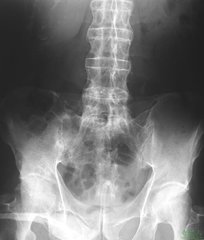

第二、影响女性的分娩:在生活中一些患有强直性脊柱炎的女性患者,疾病对女性患者较大的危害就是影响女性的分娩,由于强直性脊柱炎的耻骨联合多数出现侵蚀性软骨炎性病理改变,强直性脊柱炎初期耻骨联合关节软骨炎性坏死,坏死骨组织吸收,强直性脊柱炎晚期骶髂关节融合,耻骨联合融合,这样会造成妇女分娩时骨盆骨缝无法打开,分娩困难,产生严重的影响。

第三、使人残疾:一旦患有强直性脊柱炎,子患病后病情较严重的后果就是由于患者的脊柱强直及髋关节畸形而导致患者致残,因此在早期强直性脊柱炎,即畸形尚未形成,也就是未出现骨性强直以前,就应防患于未然。